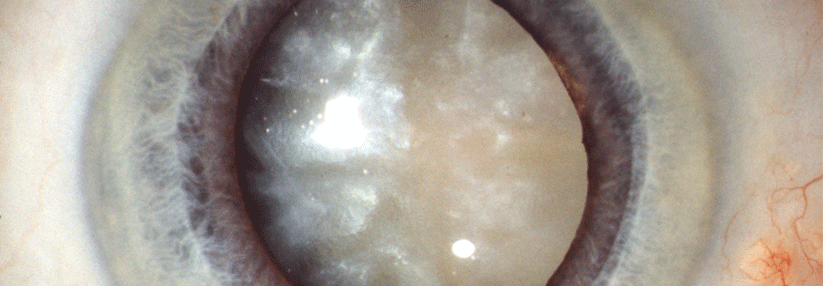

Grauer Star: Operation sorgt für mehr Sicherheit im Straßenverkehr

Wird der Graue Star operiert, gewinnt die Welt des Patienten nicht nur ihre Farbenpracht zurück. Der Linsenersatz steigert auch die Verkehrssicherheit.